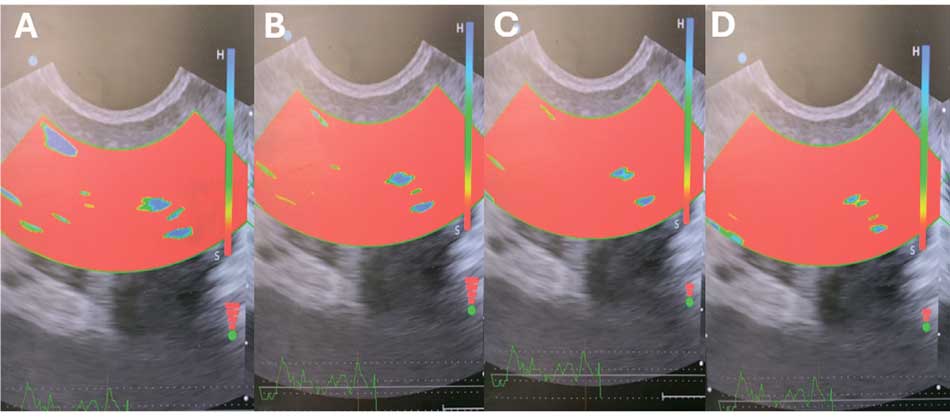

Рис. 2. Динамика картины соноэластографии предстательной железы в группе 3 до и после лечения: А – 0 неделя; В – 18 неделя; С – 30 неделя; D – 54 неделя

Fig. 2. Dynamics of the sonoelastography pictures of the рrostate in group 3 before and after treatment: A – 0 week; B – 18th week; C – 30th week; D – 54th week

По данным КЭ у пациентов с бактериальным и воспалительным ХП/СХТБ преобладали сочетания жестких участков и зон воспалительного отека (2-й эластотип по G. Xu) [14], тогда как при невоспалительном варианте фиксировались преимущественно зоны стандартной эластичности (3-й эластотип). В режиме допплерографии (ДГ) характерным было снижение выраженности сосудистого рисунка и линейной скорости кровотока; при обострении отмечалось венозное полнокровие.

В динамике (18–54-я недели) во всех группах зафиксировано уменьшение числа кальцинатов и зон фиброза, рост областей нормальной эластичности и увеличение скоростных показателей артериального кровотока. Наиболее выраженные положительные изменения регистрировались в третьей группе (рис. 2). Межгрупповой анализ показал преимущество группы 3 над первой и второй по большинству изучаемых параметров, особенно в отдаленные сроки наблюдения. Объем ПЖ достоверно уменьшался с 18-й недели; при этом статистически значимые различия между группами фиксировались преимущественно во второй группе, где положительная динамика была менее выраженной.